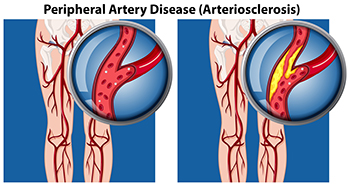

Causes and Diagnosis of Peripheral Artery Disease

Peripheral artery disease, or PAD, poses significant challenges for foot health, stemming from restricted blood flow to the lower extremities. This condition, often caused by atherosclerosis, involves the buildup of fatty deposits in the arteries, leading to narrowed or blocked blood vessels. The diminished blood supply to the feet can result in various symptoms, including pain, cramping, numbness, and weakness, particularly during physical activity. Left untreated, PAD can contribute to serious complications such as foot ulcers, infections, and delayed wound healing. Diagnosing PAD typically involves a comprehensive evaluation by a podiatrist. This process includes a thorough medical history review, assessment of risk factors such as smoking and diabetes, and a physical examination focused on evaluating circulation in the legs and feet. Specialized diagnostic tests, such as ankle-brachial index, or ABI measurement, Doppler ultrasound, and angiography, may also be employed to confirm the diagnosis and determine the extent of arterial blockages. If you are experiencing any of the foot symptoms mentioned above, it is suggested that you consult a podiatrist who can accurately diagnose and offer relief solutions for PAD.

Peripheral artery disease can pose a serious risk to your health. It can increase the risk of stroke and heart attack. If you have symptoms of peripheral artery disease, consult with Dr. James Kutchback from James Kutchback, DPM, ABLES, CWS-P. Our doctor will assess your condition and provide you with quality foot and ankle treatment.

Peripheral artery disease (PAD) is when arteries are constricted due to plaque (fatty deposits) build-up. This results in less blood flow to the legs and other extremities. The main cause of PAD is atherosclerosis, in which plaque builds up in the arteries.

Peripheral Artery Disease

Peripheral artery disease (PAD), or peripheral arterial disease, is a circulatory problem in which there is a reduction of blood flow to the limbs due to narrowed arteries. When peripheral artery disease develops, the extremities do not receive enough blood flow; this may cause symptoms to develop such as claudication, or leg pain when walking. The legs are the most common site of peripheral artery disease.

Claudication, or leg pain when walking, is one of several symptoms that can develop due to peripheral artery disease. Other symptoms caused by the disease include painful cramping in the hips, thighs, or calves after certain activities; leg numbness or weakness; coldness in the lower leg or foot; sores on the lower extremities that do not heal; hair loss on the lower extremities; and a missing or weak pulse in the lower extremities. In more severe cases, pain may even occur when the body is at rest or when lying down.

Peripheral artery disease is typically caused by atherosclerosis, a condition in which fatty deposits build up in the arterial walls and reduce blood flow. Smoking, diabetes, obesity, high blood pressure, and high cholesterol are some of the risk factors for peripheral artery disease.

Peripheral artery disease (PAD) can potentially lead to poor circulation in the lower extremities. PAD is a condition that causes the blood vessels and arteries to narrow. In a linked condition called atherosclerosis, the arteries stiffen up due to a buildup of plaque in the arteries and blood vessels. These two conditions can cause a decrease in the amount of blood that flows to your extremities, therefore resulting in pain.